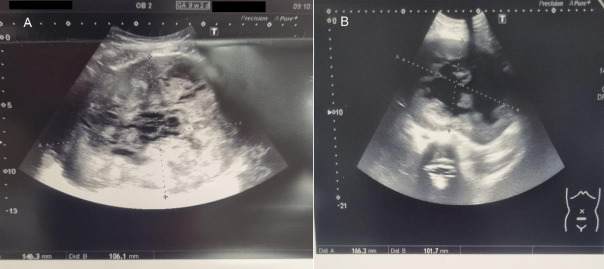

The management of symptomatic uterine fibroids during pregnancy is a challenging situation. In some cases, surgical therapy can be required. Reports indicate that both laparotomy and laparoscopy are safe methods. However, laparoscopy is associated with less morbidity. This paper describes the case of a 31-year-old woman with a symptomatic uterine fibroid which was removed by gasless laparoscopy.

Abstract Image